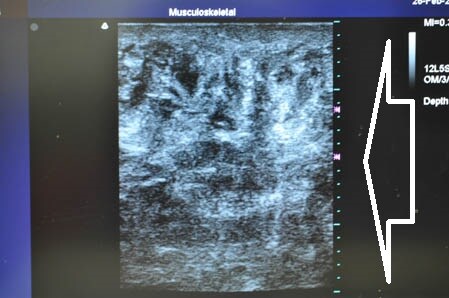

左も同様に見てみましょう。

↓ ↓ ↓